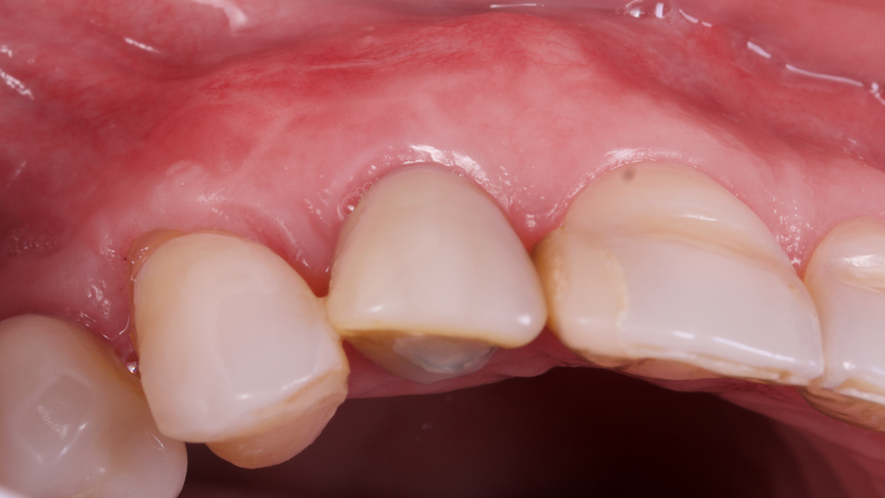

A restauração imediata pode apresentar algumas vantagens, como encurtar o tempo de tratamento, eliminar o uso de PPP ou provisórios ligados a dentes adjacentes, alta aceitação do paciente, eliminação da reabertura do implante e benefícios estéticos, sociais e psicológicos. A preservação do osso e das papilas dos dentes adjacentes ainda é citada como uma vantagem desta técnica5.

Os implantes Cone Morse foram criados com o intuito de minimizar problemas recorrentes na prática clínica odontológica, buscando maior segurança e longevidade das próteses fixas sobre os implantes e mostrando grandes resultados na estética6. O conceito Cone Morse apresenta vantagens protéticas significativas em comparação aos implantes hexágonos, principalmente em elementos unitários anteriores, tendo em vista que a longevidade da estética gengival é de suma importância, demonstrando qualidades clínicas, biológicas e biomecânicas superiores7.

Este trabalho tem como objetivo relatar um caso clínico de exodontia minimamente invasiva de um incisivo lateral superior com fratura radicular, realizando implante imediato em alvéolo pós-extração, enxerto de tecido conjuntivo subepitelial e osso bovino liofilizado para preenchimento de GAP, prontamente à instalação de pilar reto e provisório imediato.